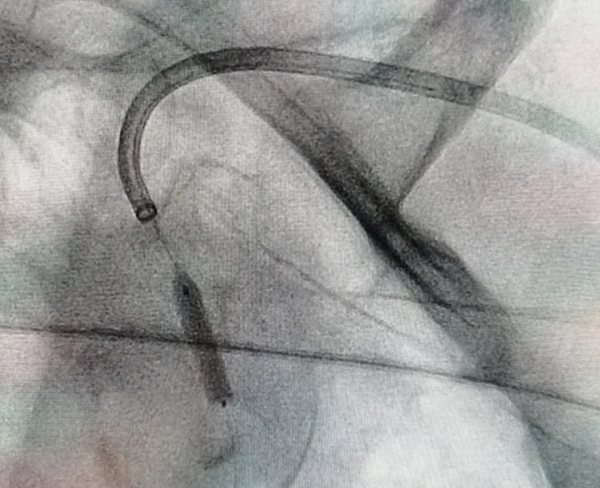

在前期充分準備的基礎上,由張志勇主任主刀歷時短短1.5小時,透過左側橈動脈入路,成功實現了左側鎖骨下動脈閉塞再通,術後患者左上臂血壓即刻恢復,頭暈症狀緩解。

術後造影顯示左側鎖骨下動脈再通,血流完全恢復 術後造影顯示左側鎖骨下動脈再通,血流完全恢復